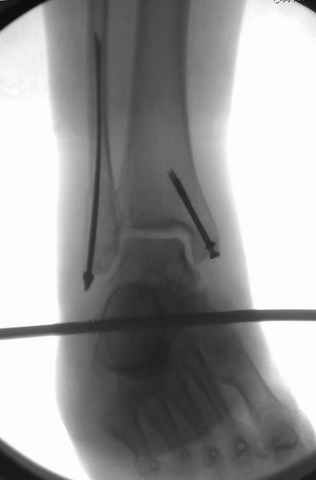

Второй случай сделан из одного разреза

На прямой проекции послеоперационного Рг макроскопически все выглядит очень анатомично, при микроскопическом ( :-)) ) рассмотрении можно все-таки заметить вальгизацию тарана, суставная щель в латеральном отделе сустава несколько уже , чем в медиальном при отсутствии латерального смещения тарана. У меня был аналогичный случай (без LISS , без мини доступа) с вальгусным наклоном тарана при восстановленном ankle mortise при последовательном наблюдении с интервалами в 6-8 недель в послеоперационном периоде отмечалось прогрессирующее сужение суставной щели в латеральном отделе сустава, закончившееся посттравматическим ОА, к счастью боли умеренные, купируемые аналгетиками или своими эндорфинами:-))(активная пациентка, у которой нет времени на болезни....) Какова жизненная ситуация в приведенном вами случае? И последнее, что я хотел бы прояснить для себя - фиксация внутренней лодыжки: я обычно комбинирую фиксацию компрессирующим винтом со спицей - по идее ротационная стабильность должна быть лучше, чем один винт, каковы ваши наблюдения в этом плане?

Pilon fracture:

конец малоберцевой кости, к нему прикрепляется латеральный суставной фрагмент дистального эпиметафиза большеберцовой кости (как на снимке)

и таранная кость, которые при репозиции малоберцовой кости репонируются автоматически.